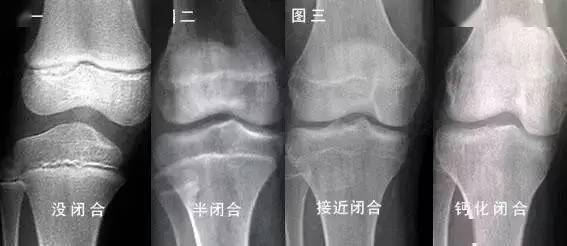

“断骨增高”手术风险大,国内管控已近20年(人民日报健康客户端记者 王艾冰)4月10日,“女子60万元国外断骨增高陷维权困局”事件引发关注。“断骨增高又叫肢体延长术,是一种通过手术人为截断下肢长骨,并在断骨处安装外固定支架或植入磁控髓内钉,通过缓慢牵拉刺激骨骼再生的手术形式。在牵拉过程中,断骨间隙会逐渐形成...